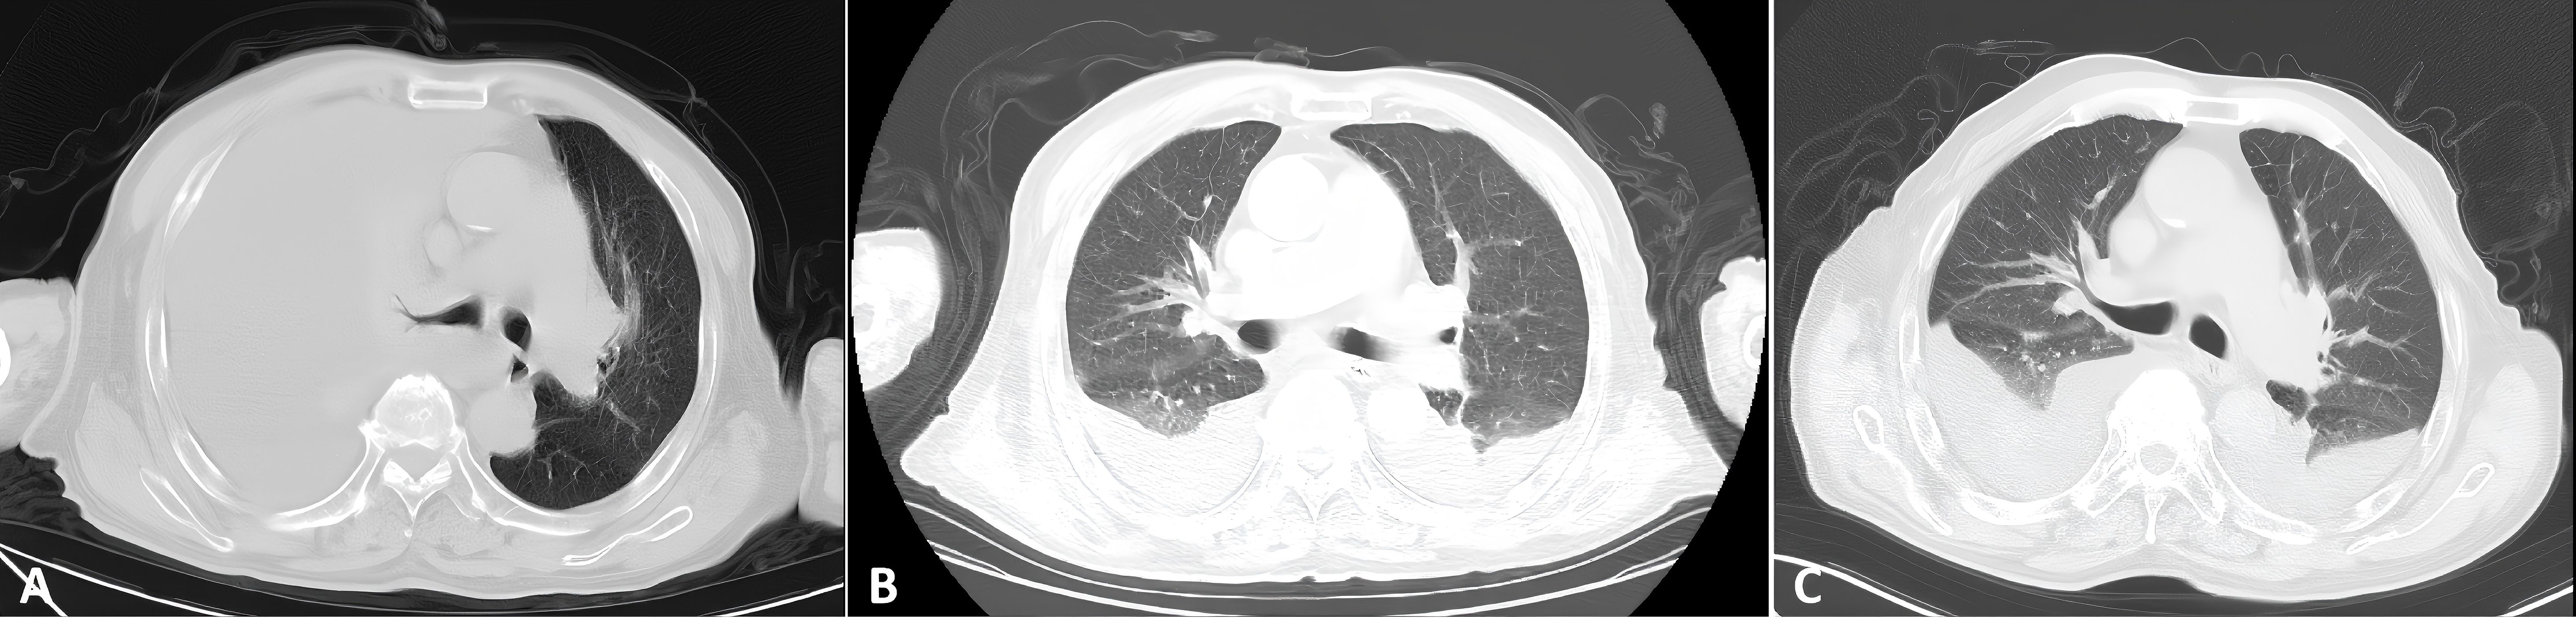

Fluid overload–associated large B-cell lymphoma (FO-LBCL) is a rare lymphoma that primarily involves serous body cavities (pleural, peritoneal, and pericardial spaces) without forming solid masses. Because FO-LBCL is uncommon, patients typically present with nonspecific symptoms—most frequently dyspnea from effusion—hindering early recognition and diagnosis. This study presents two cases of FO-LBCL and reviews the clinical characteristics, treatment regimens, and prognosis of 57 patients with FO-LBCL. Results showed that serous effusions involved the pleural cavity in 84.2% of cases, the pericardial cavity in 31.6%, and the peritoneal cavity in 21.1%. The most frequent presenting symptom was dyspnea (55.8%); other reported symptoms included chest tightness, gastric discomfort, fatigue, and lower-limb edema, reflecting respiratory, gastrointestinal, circulatory, and systemic involvement. Chemotherapy was the primary treatment (56.1%), most commonly the R-CHOP regimen. Univariate analysis identified the following factors as significantly associated with outcome: CD20 expression (P = 6 × 10-7), absence of CD138 expression (P = 0.0009), age > 65 years (P = 0.0015), LDH ≤500 U/L (P = 0.0064), presence of pleural effusion (P = 0.0099), CD79a expression (P = 0.0395), and use of rituximab-containing chemotherapy regimens (P = 0.0049). Our objectives are to characterize FO-LBCL comprehensively, clarify its differential diagnosis and management options, and address current gaps in clinical knowledge about this entity.